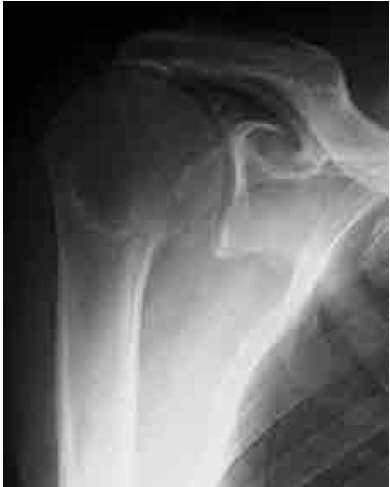

61歳の男性。半年前より続く右肩の挙上不全と可動時痛を主訴として来院した。右肩関節単純X線正面(true AP)像を示す。正しいのはどれか。3つ選べ。

a. 肩峰下に骨棘を認める。

b. 腱板断裂の合併はない。

c. 上腕骨頭の大結節は消失している。

d. 肩甲上腕関節に関節症変化を認める。

e. 解剖学的人工肩関節全置換術の適応である。

正解:a, c, d